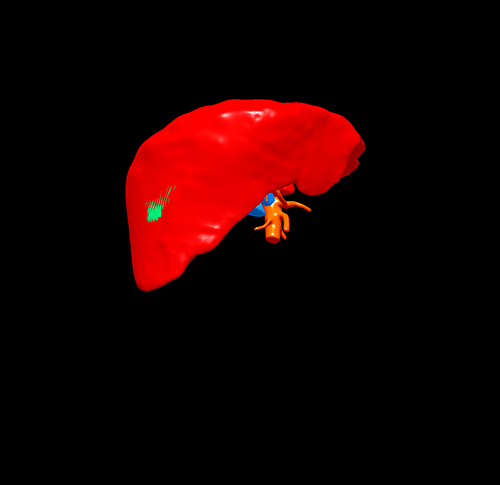

S6肝癌 胆囊结石--腹腔镜右肝部分切除 胆囊切除